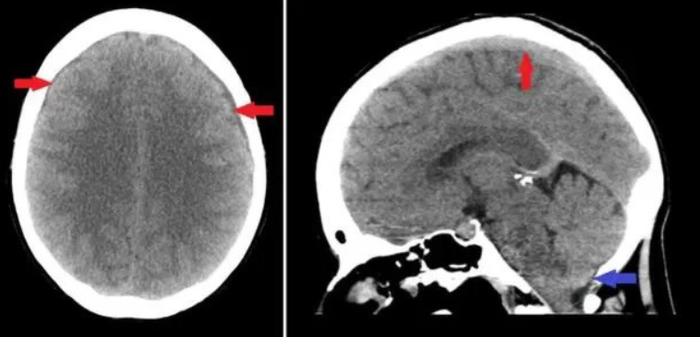

Sau khi tiến hành các xét nghiệm chuyên sâu, đội ngũ y tế đưa ra chẩn đoán: bệnh nhân bị rò rỉ dịch não tủy lưu lượng cao kèm theo nhiễm trùng nội sọ nghiêm trọng. Theo các bác sĩ, đây là tình trạng rất nguy hiểm. Dịch não tủy vốn có nhiệm vụ bảo vệ não và tủy sống. Khi lớp màng bảo vệ bị tổn thương, dịch não tủy có thể rò rỉ ra ngoài qua khoang mũi. Nếu không được phát hiện và xử lý kịp thời, vi khuẩn dễ dàng xâm nhập vào hệ thần kinh trung ương, dẫn đến nhiễm trùng não, thậm chí tử vong.

Ở bước đầu tiên, bệnh nhân được thực hiện thủ thuật dẫn lưu dịch não thất - màng bụng nhằm giảm áp lực nội sọ và kiểm soát tình trạng nhiễm trùng. Sau khi các chỉ số sức khỏe dần ổn định, các bác sĩ tiếp tục tiến hành phẫu thuật nội soi qua đường mũi để xử lý vị trí rò rỉ.

Trong ca phẫu thuật này, mô tự thân của chính bệnh nhân được sử dụng để bịt kín khu vực rò rỉ dịch não tủy một cách chính xác. Nhờ sự phối hợp chặt chẽ giữa các chuyên khoa, ca phẫu thuật cuối cùng đã diễn ra thành công, giúp bệnh nhân vượt qua giai đoạn nguy hiểm.